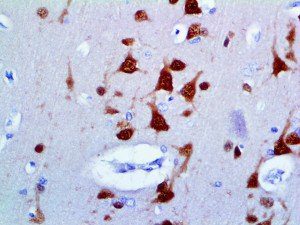

It is the ICU physician who is most likely to witness one of the deadliest manifestations of the abnormal immunological response, the cytokine storm syndrome (CSS). This response is also referred to by some as the cytokine release syndrome (CRS). CSS is characterized by continuous activation and expansion of macrophage and lymphocyte populations, which secrete large amounts of cytokines, causing the cytokine storm. This massive cytokine release is akin to hemophagocytic lymphohistiocytosis (HLH) disease, a syndrome characterized by initial unchecked and persistent activation of cytotoxic T lymphocytes and NK cells.

Clinical and laboratory manifestations of HLH include fever, enlarged liver and/or spleen, neurologic dysfunction, coagulopathy, liver dysfunction, cytopenias (i.e., low levels of erythrocytes, leukocytes, and/or platelets), hypertriglyceridemia, hyperferritinemia, hemophagocytosis, and eventually diminished NK cell activity as the immune system becomes progressively paralyzed. HLH can be familial (primary HLH) or secondary to another disease process (sHLH), such as rheumatic disease, in which it is referred to as macrophage activation syndrome (MAS, characterized by elevated ferritin).